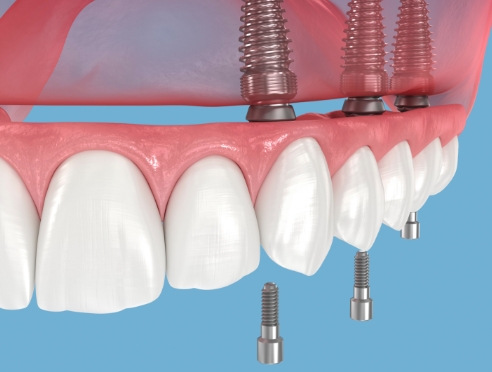

임플란트는 정확한 진단과 계획을 기반으로

여러 단계를 거쳐 진행되는 치료입니다.

환자분의 구강 상태에 맞춰

단계별로 안전하게 진행됩니다.

계획된 가이드에 따라 안정적으로

임플란트를 식립합니다.